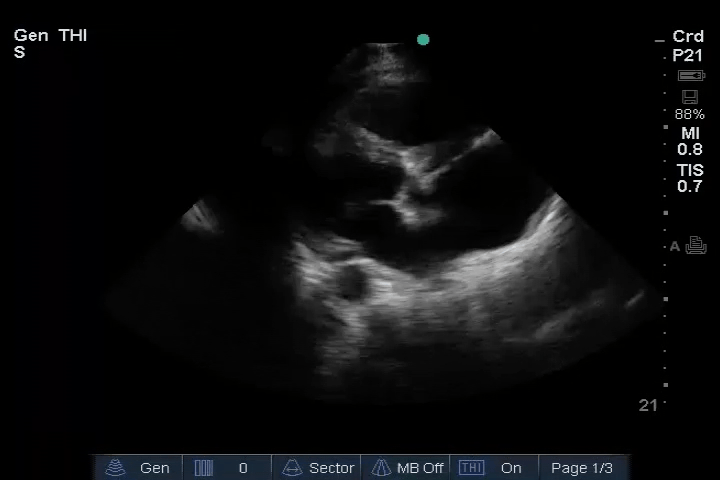

12_Heart_PLAX – Dilated RV, RA embolus

13_Heart_PSAX – Dilated RV